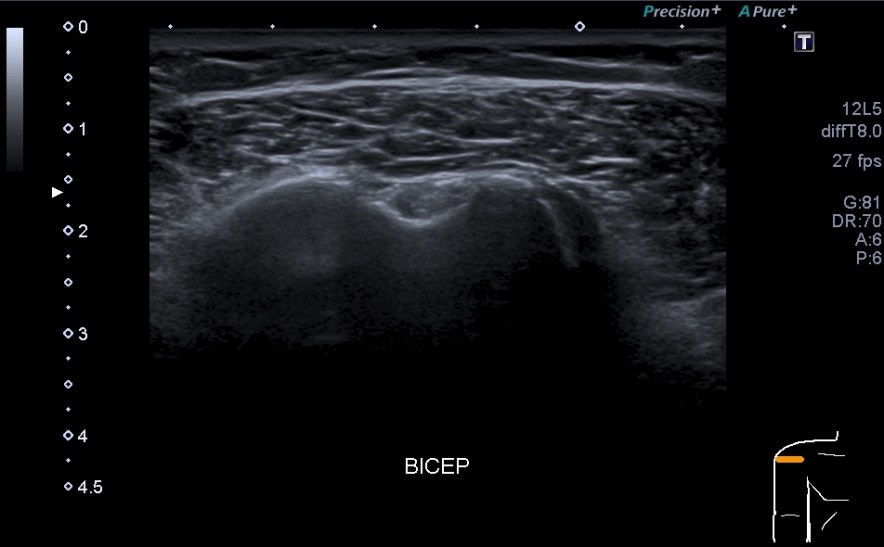

1.Tendón del biceps, cabeza larga.

Situada en la corredera bicipital, vas a ver el bíceps como una estructura hiperecogénica, redondeada situado en el valle de la corredera. Observa como la imagen superior indica ausencia de líquido y normalidad y la inferior relación entre la anatomía y la patología donde el líquido rodea el tendón en relación con una posible tenosinovitis.